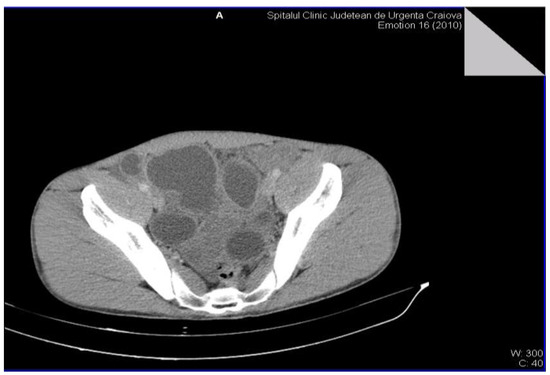

Figure 2.

Multiple intra-abdominal hydatid cysts.

Figure 3.

Intra-abdominal hydatid cysts.

The definitive diagnosis of the retroperitoneal hydatid cyst was based on the anamnesis, clinical examination and paraclinical examinations, including serological examinations. The medical history of the patients was insignificant, but most of them were from rural areas and confirmed the close interaction with animals (sheep, goats, dogs). The clinical examination very rarely raises the suspicion of retroperitoneal hydatid cyst, the examinations of other systems and organs being normal. Most of the biological investigations were within normal limits. The serological examination by detecting the immunoglobulin G antibody by the ELISA method (enzyme-linked immunosorbent assay) was positive in all cases, showing high sensitivity and specificity and was only performed after raising the suspicion of hydatid cyst by imaging methods. Non-invasive imaging paraclinical investigations for the diagnosis of the disease were: abdominal (or regional) ultrasound, CT scan (computed tomography) and MRI (magnetic resonance imaging) that proved a high sensitivity. The presence of daughter cysts, hydatid sands, and floating membrane can confirm the diagnosis of hydatid cyst [6,7]. Abdominal ultrasound established the diagnosis in the case of 4 patients, and in the case of two patients it raised the suspicion of retroperitoneal hydatid cyst. The CT examination was carried out in 5 patients, for diagnostic purposes or for the remote evaluation of the lesions. In 2 patients, the tomographic diagnosis was accidental, without clinical or paraclinical suspicion of abdominal hydatid cysts and revealed their single or multiple presence, either only retroperitoneally or also intraperitoneally (Figure 2 and Figure 3).